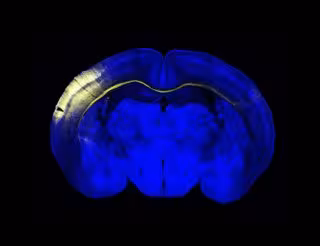

Archivo - Sección horizontal del cerebro del ratón. Un grupo de neuronas de la corteza iluminadas en amarillo extienden sus axones a través del cuerpo calloso para conectar con el hemisferio contralateral.

Archivo - Sección horizontal del cerebro del ratón. Un grupo de neuronas de la corteza iluminadas en amarillo extienden sus axones a través del cuerpo calloso para conectar con el hemisferio contralateral. - CNB/ CSIC - Archivo